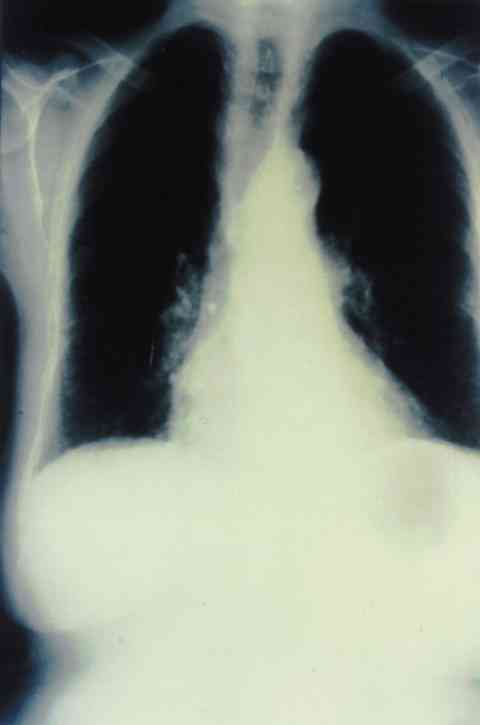

Figura 2

RX TÓRAX EN LA QUE SE OBSERVAN ADENOPATÍAS HILIARES JUNTO A UN PATRÓN INTERSTICIAL EN AMBAS BASES PULMONARES.